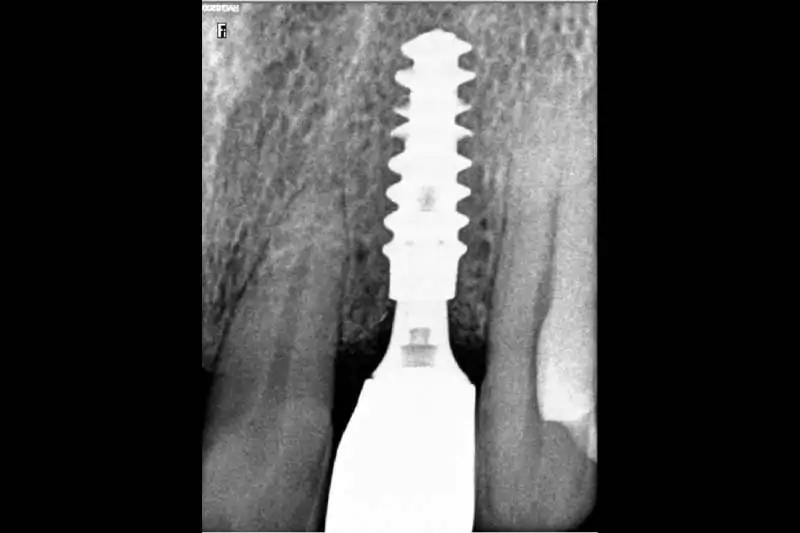

Smilex Advanced Dental Care proudly offers world-class Same Day Dental Implants Treatment in India, enabling you to regain full dental function in just one visit. Whether you've lost a single tooth or multiple, our expert implantologists use advanced digital scans, CBCT imaging, and CAD/CAM-supported restorations to provide precise, long-lasting results.

Same Day Implantology is an advanced dental procedure that allows for the replacement of missing teeth with dental implants in just a single appointment. Unlike traditional methods that involve multiple visits and a lengthy healing period, Same Day Dental Implants In India offer a more efficient and convenient solution, providing immediate results. This process involves precise digital planning to ensure the correct placement of implants, improving both the speed and success rate of the procedure. Additionally, if you’re considering a complete smile transformation, understanding the Full Mouth Dental Implant Cost In India will help you make an informed decision about this quick and effective treatment option. With modern technology and expert care, you can restore your smile in no time while maintaining long-term oral health.

Teeth extraction (if necessary) and implant placement.Temporary crowns or bridges attached for immediate function and aesthetics.